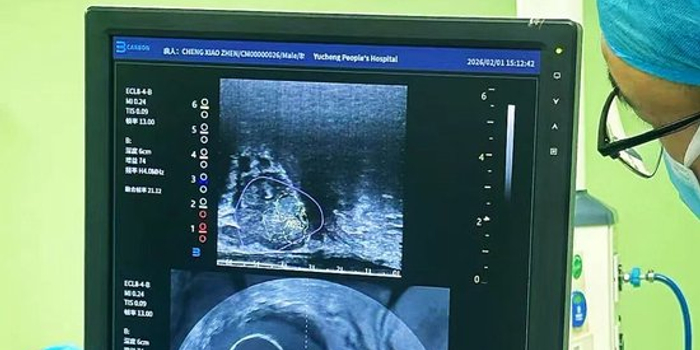

主刀医师井学辉本次采用的 “磁共振融合B超”技术,堪称前列腺穿刺领域的“病灶定位导航仪”。该技术巧妙地将术前高分辨率磁共振(MRI)图像与术中实时B超图像进行三维融合。可以清晰识别磁共振提示的可疑病灶(靶目标),同时在B超实时引导下,将穿刺针精准抵达目标区域。整个过程仅用时15分钟。这种精准直击病灶的穿刺方式,极大提高了早期局限癌的检出率和定位准确性,同时减少了不必要的穿刺针数,降低了感染率。